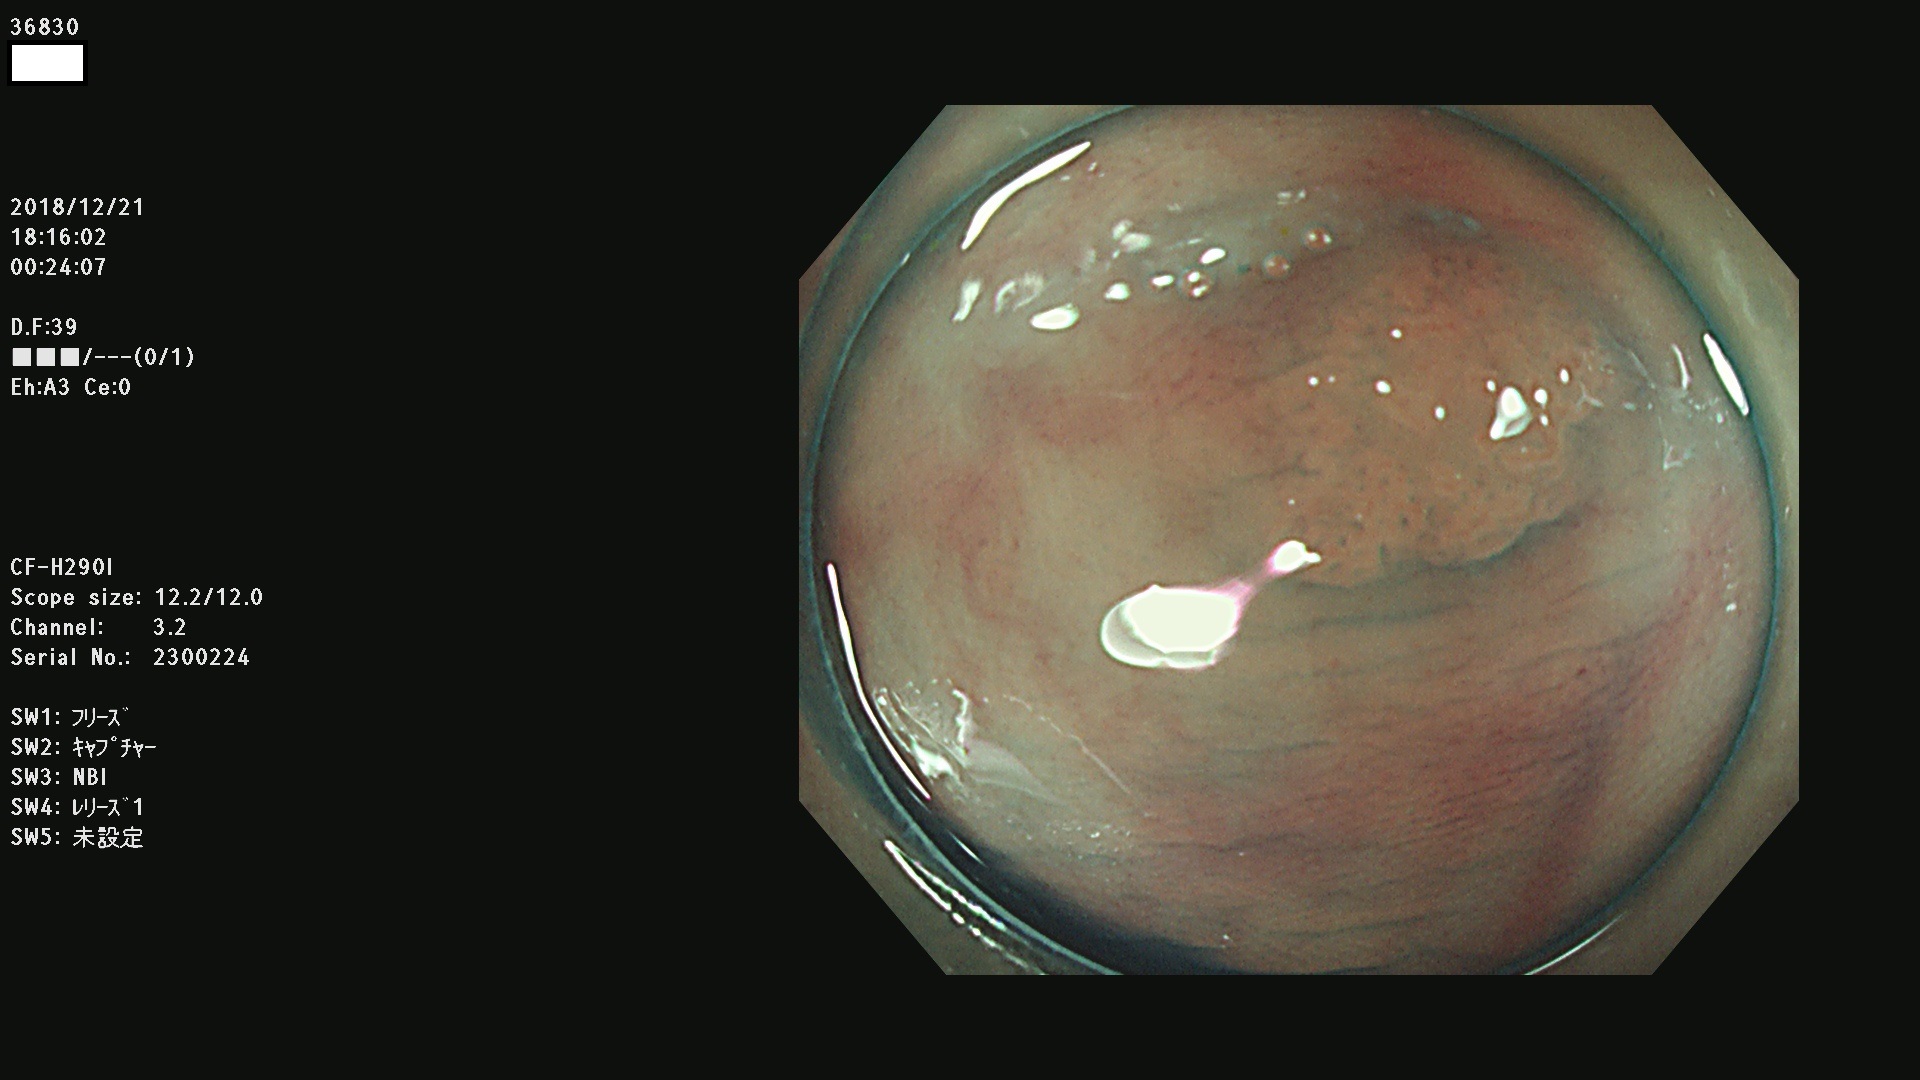

36804 36806 36807 36808 36809 36810 36811 36813 36815 36816 36817 36818 36820 36821 36822 36824 36825 36826 36828 36829 36830 36831 36832 36833 36834 36835 36837 36840 36841 36842 36845 36846 36848 36849 36851 36852 36853 36854 36855 36857 36859 36860 36861 36862(SSAPのみ) 36863 36864 36866 36868 36869 36870 36873 36875 36877 36878 36879 36881 36882 36883 36884 36885 36886 36887 36888 36889 36891 36892 36893 36894 36895 36896 36897 36898 36899

発見困難で危険性の高い平坦型病変(上記100名より抽出)